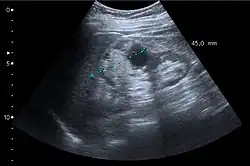

Unspecific cortical lesion on CT scan is confirmed cystic and benign with contrast-enhanced renal ultrasonography.

A CT scan is the first choice modality for workup of solid masses in the kidneys. Nevertheless, hemorrhagic cysts can resemble renal cell carcinomas on CT, but they are easily distinguished with Doppler ultrasonography (Doppler US). In renal cell carcinomas, Doppler US often shows vessels with high velocities caused by neovascularization and arteriovenous shunting. Some renal cell carcinomas are hypovascular and not distinguishable with Doppler US. Therefore, renal tumors without a Doppler signal, which are not obvious simple cysts on US and CT, should be further investigated with contrast-enhanced ultrasound, as this is more sensitive than both Doppler US and CT for the detection of hypovascular tumors.[3]

Cortical solid mass, which later was shown to be renal cell carcinoma. Measurement of the solid mass on the US image is illustrated by '+' and a dashed line.[3]